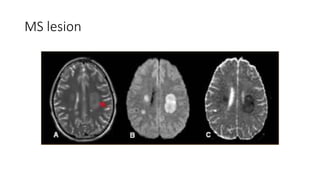

MS lesion

• Optic atrophy,, MS